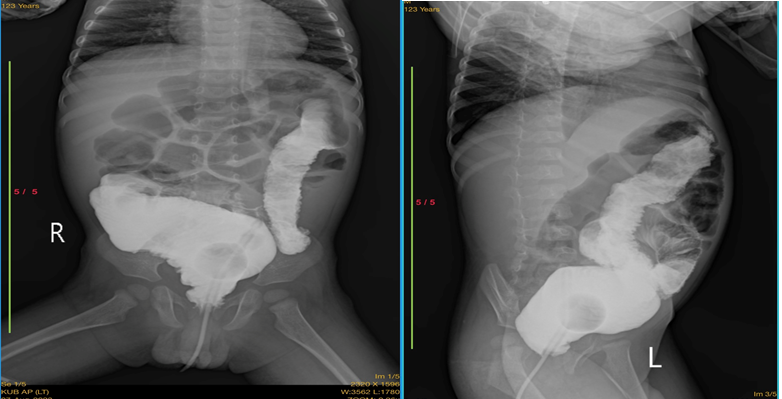

Một số hình ảnh của một bệnh nhi 16 tháng tuổi bị phình đại tràng bẩm sinh được phẫu thuật hạ đại tràng xuyên hậu môn trong trực tràng tại khoa Ngoại Tổng hợp - Bệnh viện đa khoa tỉnh Quảng Trị

XQ trước mổ